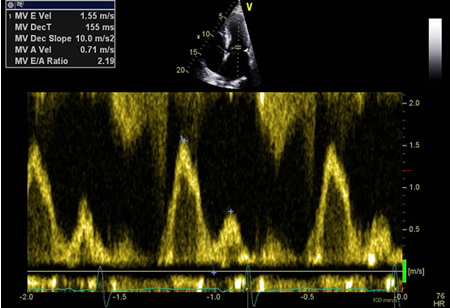

Pseudonormalização de fluxo de entrada mitral do E:A

Do acervo de Dr Jessica Webb; usado com permissão